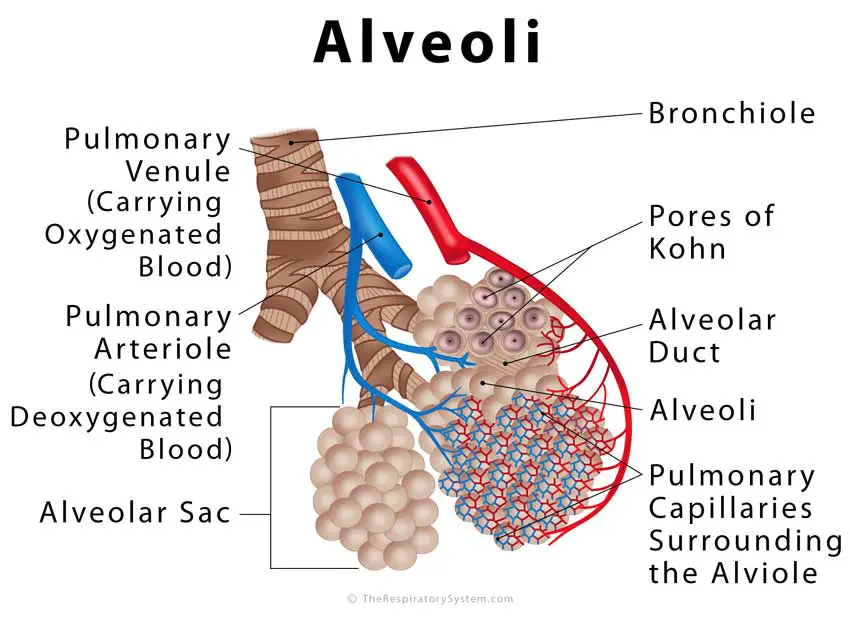

Www.therespiratorysystem.com Alveoli | Human Body Anatomy, Human

www.pinterest.com

www.pinterest.com

alveoli respiratory system anatomy lungs function exchange gas definition human respiration biology location surface diagram alveolus capillaries pulmonary lung where

Alveoli Definition, Location, Anatomy, Function, Diagrams

www.therespiratorysystem.com

www.therespiratorysystem.com

alveoli respiratory system anatomy lungs function exchange gas human definition location surface diagram alveolus capillaries pulmonary lung where wall respiration